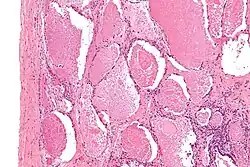

Intermediate magnification micrograph of pulmonary alveolar proteinosis. H&E stain.

Lung washings or tissue for histopathologic analysis are most commonly obtained using bronchoalveolar lavage and/or lung biopsy.[13] Characteristic biopsy findings show filling of the alveoli (and sometimes terminal bronchioles) with an amorphous eosinophilic material, which stains strongly positive on PAS stain and the PAS diastase stain. The surrounding alveoli and pulmonary interstitium remain relatively normal.[14] Electron microscopy of the sample, although not typically performed due to impracticality, shows lamellated bodies representing surfactant.[15] An alternative diagnosis with similar histomorphologic findings is Pneumocystis jirovecii pneumonia.[15]

Lung washings characteristically yield a fluid which is "milky"composition. Under the microscope, samples show 20-50 micrometer PAS-positive globules on a background of finely granular or amorphous PAS-positive material. There is typically a low numbers of macrophages and inflammatory cells (although this is variable).[14][15]